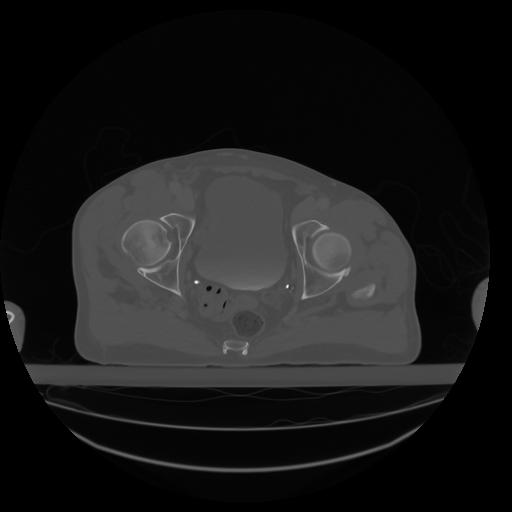

27 CUERPO,CE,Axial,3.0,CUERPO,,